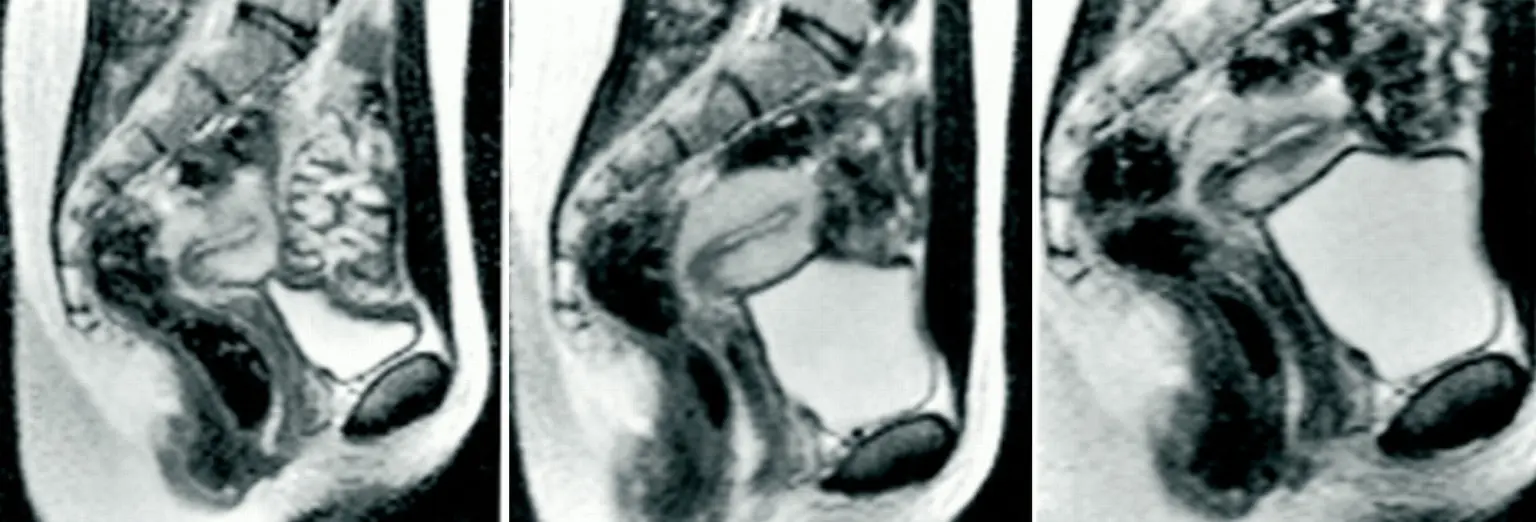

The images produced during the experiment provided remarkable insight into how the body works during intercourse. One of the most surprising discoveries involved the shape of the male anatomy during penetration.

Instead of remaining straight, the images showed that the penis bends inside the vaginal canal. The shape closely resembled a curved or boomerang form. This bending allows the anatomy of both partners to align naturally during intercourse.

This finding contradicted centuries of assumptions that had appeared in early medical drawings and anatomical studies. It also demonstrated that the body adjusts in complex ways during intercourse to accommodate natural movement and positioning.

The MRI scans also revealed new information about how the female body responds during intercourse. Researchers observed changes in the uterus and surrounding structures when arousal occurred.

One key observation showed that during arousal without intercourse, the uterus rises and the front wall of the vagina lengthens. These adjustments prepare the body for intercourse and help accommodate penetration.

However, the scans indicated that the uterus itself does not increase in size during intercourse. This detail helped clarify how female anatomy behaves during the process and corrected several misunderstandings that had circulated in earlier medical discussions.